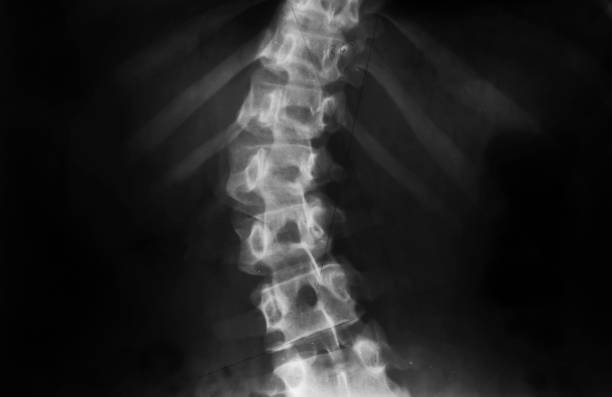

척추측만증은 허리가 옆으로 휘어진 상태를 나타내는 질환으로, 특히 청소년기에 많이 발생하는 허리의 변형이며 척추의 측만(옆으로) 휘어짐을 특징으로 합니다. 이 질환은 주로 10도 이상의 각도로 허리가 휘어질 때 측만증으로 분류됩니다.

척추측만증은 초기에는 치료가 뚜렷하게 정해져 있지 않으며, 조기 발견과 조기 치료가 중요합니다. 20도 미만의 각도로 허리가 휘어진 경우에는 운동, 체조, 바른 자세 유지, 근육 강화 운동 등으로 관리할 수 있습니다. 그러나 20도 이상이 되면 더 진행될 가능성이 높으므로 보조기를 사용하거나 각도가 50도 이상일 때 허리를 교정하는 수술을 고려해야 합니다.

척추측만증의 수술은 어떤 방식으로 이루어지나요?

척추측만증의 수술은 주로 어린 아이들에게 권장되며, 척추 뼈가 아직 유연한 상태일 때 수행하는 것이 효과적입니다. 이 수술은 나사나 못을 사용하여 허리를 교정하는 것으로, 치과에서의 교정과 유사한 원리를 가지고 있습니다. 나사나 못을 이용하여 허리를 고정하고 철심을 사용하여 교정을 진행합니다. 이로써 허리를 바로 세우는 것이 가능하며, 수술 후에도 자연스러운 자세를 유지할 수 있습니다.